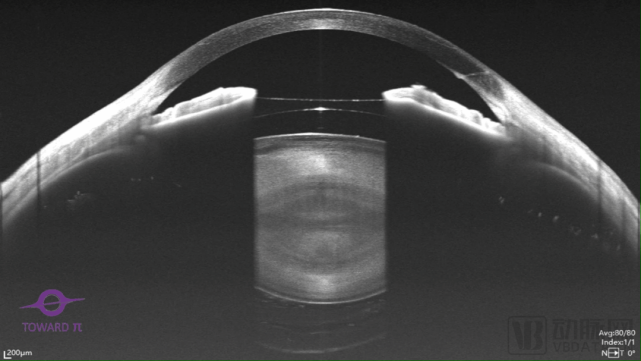

在时间更早的2020年12月,图湃医疗发布了全球首台全景前后节一体式扫频OCT产品“瑶光·星”,该产品是全球首个同时支持全景前节成像、全景后节成像和OCT血流成像的全功能产品,能够满足眼科几乎所有亚专科的不同诊断需要。

图湃“瑶光·星”全景前后节一体式眼科OCT及其全景前节成像图